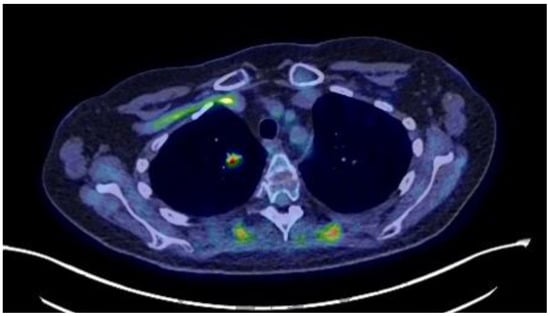

The patient developed impaired alertness, tetrapyramidal syndrome, and myopathy, and a T8 osteoporotic compression fracture was identified. Mild hypokalemia was still present (3.47 mmol/L). The endocrine team requested a biopsy of the pulmonary lesions to seek an ectopic source of ACTH, but other specialties maintained that the pulmonary lesions were of infectious origin, and a biopsy was not performed. Nevertheless, ketoconazole (escalated from 600 to 800 mg/day) and hydrocortisone (10 mg/day) were started with liver-enzyme monitoring. This reduced cortisol by about 50% from baseline, although hypercortisolemia remained present, and the hypokalemia resolved. The patient’s clinical condition improved, and she was transferred to our institution for physiotherapy and rehabilitation. A referral to our endocrine group led us to reinvestigate the pulmonary lesions, and a new 18F-FDG-PET/CT showed the persistence of a 13 mm hypermetabolic nodule (SUVmax: 6.2) in the right lower lobe (Figure 1). On our recommendation, a CT-guided biopsy was performed, which was suggestive of a carcinoid lesion. She was referred for thoracic surgery, and a right lower lobectomy with systematic lymph node dissection was performed. This permitted an R0 resection, and ketoconazole was discontinued (Figure 2). Pathology showed a 1.6 × 1.5 × 1.5 cm, carcinoid-type, typical lung NET (Ki-67: <2%; no necrosis; Thyroid Transcription Factor 1 (TTF-1): intensely positive; CD56: intense, diffuse positivity; keratin-7 partial positivity). As expected, the patient developed ACTH deficiency postoperatively and was treated with hydrocortisone 20 mg/day, with a taper over nine months. At the last follow-up, she was biochemically and hormonally normal, and the signs and symptoms of CS, including depression, had regressed. Long-term treatment involved continued physical rehabilitation, oral calcium/vitamin D, and iron treatment.

Figure 1. 18F FDG PET/CT showing a hypermetabolic region in the right lung.